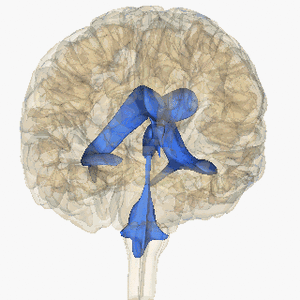

يحتوي المخ على مجموعة مكونة من أربعة بطينات (حجرات أو تجاويف صغيرة) كلها تحتوي على السائل الدماغي الشوكي فيما يعرف بالجهاز البطيني للمخ. تتصل البطينات الأربعة ببعضها وبالقناة المركزية الموجودة في منتصف الحبل الشوكي ويتم بداخل البطينات الأربعة وبشكل مستمر تكوين سائل مهم من سوائل الجسم يسمى السائل الدماغي الشوكي.

وفي ظروف أخرى يمكن أن ينشأ استسقاء الرأس عن تكوين السائل الدماغي الشوكي بمعدلات أكبر من الطبيعية فيحدث عدم التوافق بين إنتاج السائل النخاعي وامتصاصه. مما يسبب تراكمه داخل البطينات الدماغية أيضًا. بناءً على الآلية، استسقاء الرأس يمكن أن يصنف إلى استسقاء رأس متصل وغير متصل (انسداد). كلا الشكلين يمكن أن يكون إما خلقياً أو مكتسباً.